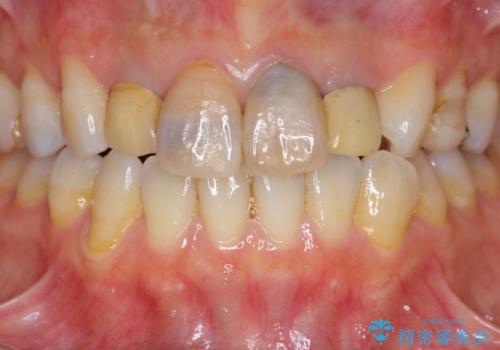

- 「黒ずんで、見栄えの悪い前歯をきれいにしたい。」と、前歯のセラミック治療を希望され来院されました。

全て根管治療のすでになされている歯の変色で、オールセラミッククラウンによる審美性の改善を計画します。